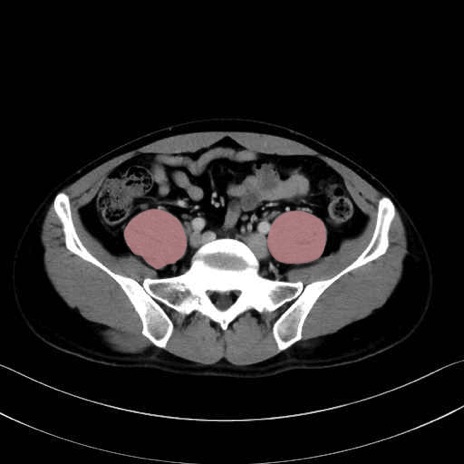

2. 腸腰筋群と骨盤底筋

大腰筋 (Psoas major)

腸骨筋 (Iliacus)